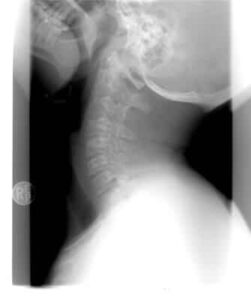

首の痛み

ストレートネックの誤解を解く!本当の原因と「BFI療法」による改善策